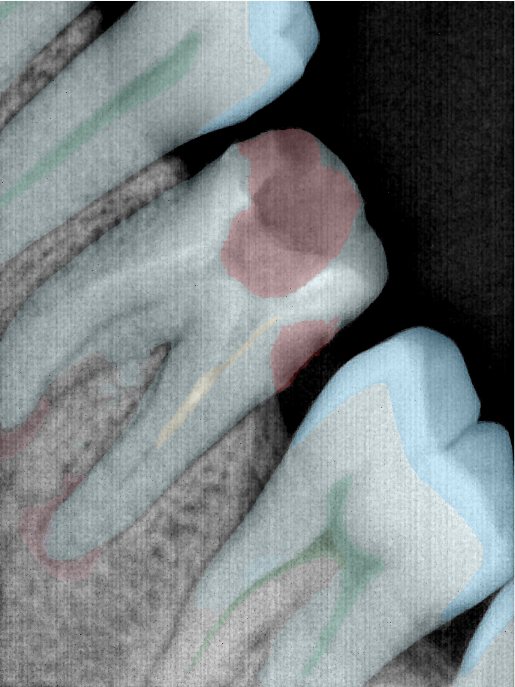

第三版算法分辨率效果比较

| 编号 | 原图 | 第一版 | 第二版 | 第三版 1216x1600 | 第三版 768x1024 | 第三版 1120x1120 |

|---|---|---|---|---|---|---|

| 131315.jpg | ![]() | ![]() | ![]() | ![]() | ![]() | ![]() |

| 131316.jpg | ![]() | ![]() | ![]() | ![]() | ![]() | ![]() |

| 131317.jpg | ![]() | ![]() | ![]() | ![]() | ![]() | ![]() |

| 131318.jpg | ![]() | ![]() | ![]() | ![]() | ![]() | ![]() |

| 131319.jpg | ![]() | ![]() | ![]() | ![]() | ![]() | ![]() |

| 131320.jpg | ![]() | ![]() | ![]() | ![]() | ![]() | ![]() |

| 131321.jpg | ![]() | ![]() | ![]() | ![]() | ![]() | ![]() |

| 131326.jpg | ![]() | ![]() | ![]() | ![]() | ![]() | ![]() |

| 131327.jpg | ![]() | ![]() | ![]() | ![]() | ![]() | ![]() |

| 131328.jpg | ![]() | ![]() | ![]() | ![]() | ![]() | ![]() |

| 131330.jpg | ![]() | ![]() | ![]() | ![]() | ![]() | ![]() |

| 131331.jpg | ![]() | ![]() | ![]() | ![]() | ![]() | ![]() |

| 131332.jpg | ![]() | ![]() | ![]() | ![]() | ![]() | ![]() |

| 131333.jpg | ![]() | ![]() | ![]() | ![]() | ![]() | ![]() |

| 131334.jpg | ![]() | ![]() | ![]() | ![]() | ![]() | ![]() |

| 131336.jpg | ![]() | ![]() | ![]() | ![]() | ![]() | ![]() |

| 131337.jpg | ![]() | ![]() | ![]() | ![]() | ![]() | ![]() |

| 131338.jpg | ![]() | ![]() | ![]() | ![]() | ![]() | ![]() |

| 131339.jpg | ![]() | ![]() | ![]() | ![]() | ![]() | ![]() |

| 131340.jpg | ![]() | ![]() | ![]() | ![]() | ![]() | ![]() |

| 131341.jpg | ![]() | ![]() | ![]() | ![]() | ![]() | ![]() |

| 131342.jpg | ![]() | ![]() | ![]() | ![]() | ![]() | ![]() |

| 131344.jpg | ![]() | ![]() | ![]() | ![]() | ![]() | ![]() |

| 131345.jpg | ![]() | ![]() | ![]() | ![]() | ![]() | ![]() |

| 131346.jpg | ![]() | ![]() | ![]() | ![]() | ![]() | ![]() |

| 131347.jpg | ![]() | ![]() | ![]() | ![]() | ![]() | ![]() |

| 131348.jpg | ![]() | ![]() | ![]() | ![]() | ![]() | ![]() |

| 131349.jpg | ![]() | ![]() | ![]() | ![]() | ![]() | ![]() |

| 131350.jpg | ![]() | ![]() | ![]() | ![]() | ![]() | ![]() |

| 131354.jpg | ![]() | ![]() | ![]() | ![]() | ![]() | ![]() |

| 131355.jpg | ![]() | ![]() | ![]() | ![]() | ![]() | ![]() |

| 131356.jpg | ![]() | ![]() | ![]() | ![]() | ![]() | ![]() |

| 131357.jpg | ![]() | ![]() | ![]() | ![]() | ![]() | ![]() |

| 131360.jpg | ![]() | ![]() | ![]() | ![]() | ![]() | ![]() |

| 131362.jpg | ![]() | ![]() | ![]() | ![]() | ![]() | ![]() |

| 131363.jpg | ![]() | ![]() | ![]() | ![]() | ![]() | ![]() |

| 131364.jpg | ![]() | ![]() | ![]() | ![]() | ![]() | ![]() |

| 131365.jpg | ![]() | ![]() | ![]() | ![]() | ![]() | ![]() |